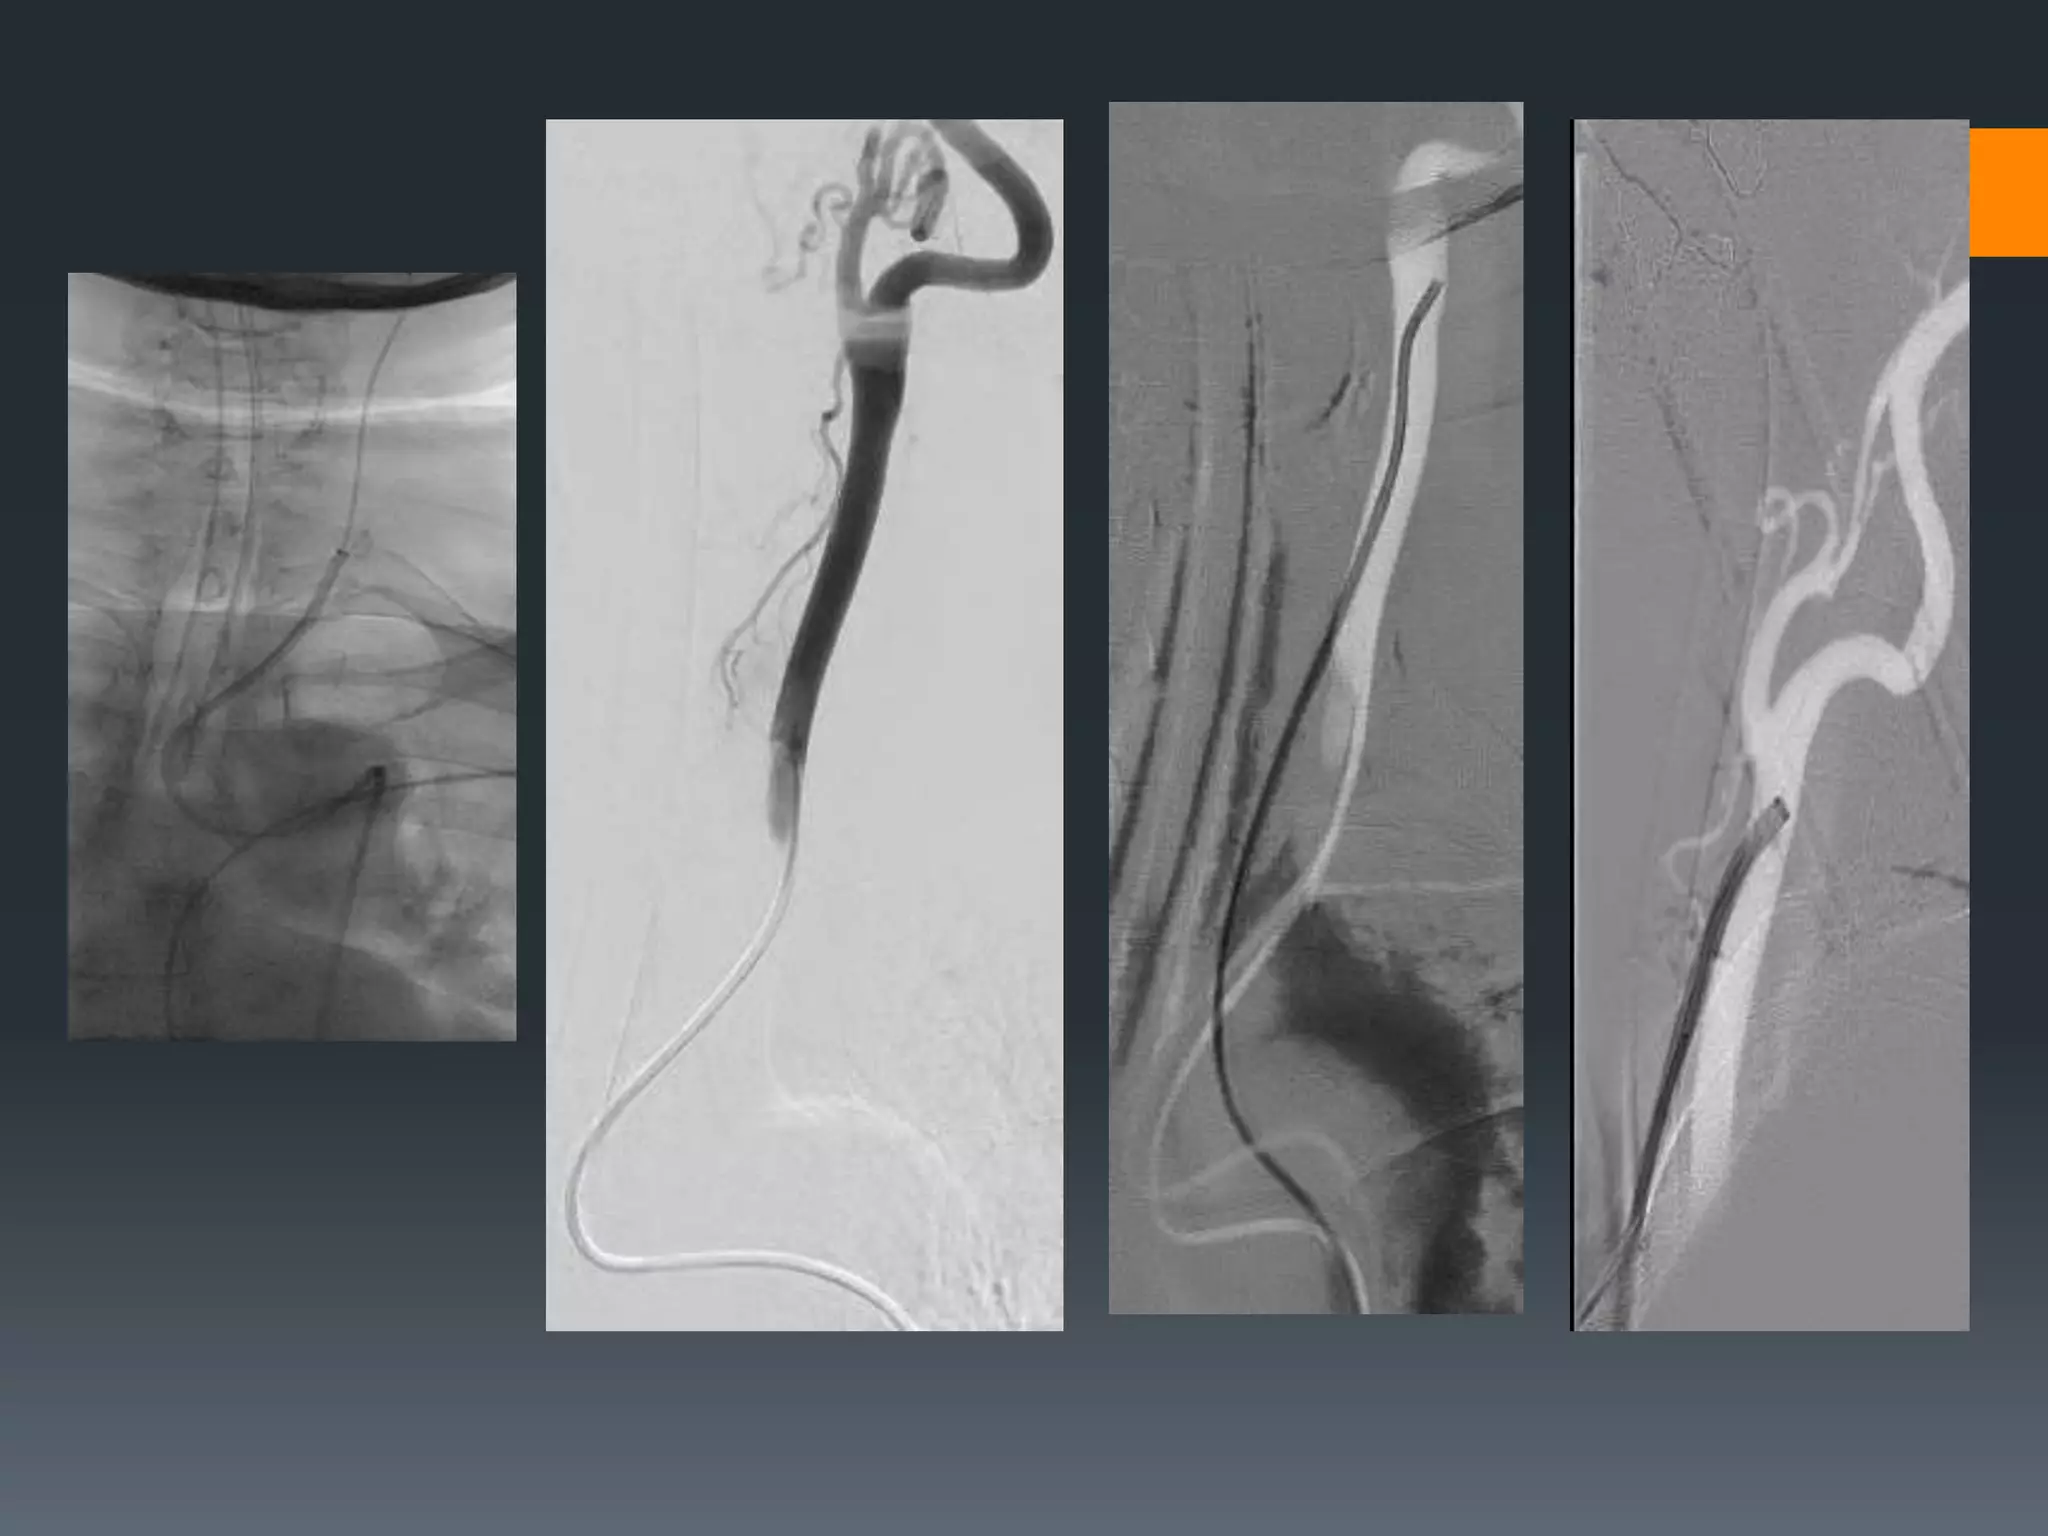

This document discusses tricks and techniques for difficult cannulations during neurointerventional procedures. It outlines strategies for accessing the aortic arch, internal carotid artery (ICA), and areas distal to aneurysms. Long sheaths, distal access catheters, and co-axial techniques are presented as options that have improved cannulation success. Guidance on sheath and catheter selection is provided for different vessel paths. The importance of catheter placement as high as possible in the ICA is emphasized. Reverse curve cannulations are also mentioned. Overall, the document stresses that careful cannulation is critical for procedural success and different strategies may be needed depending on the vessel target.